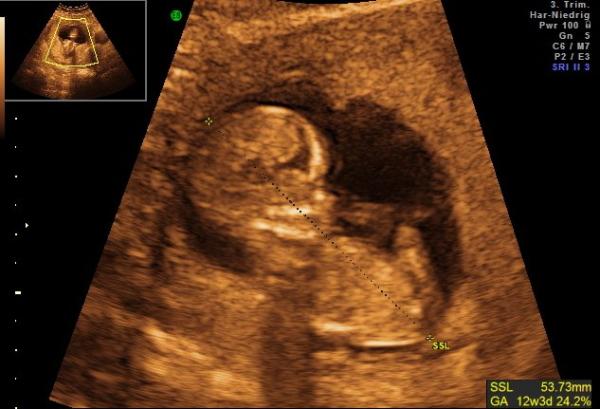

Hallo ihr Lieben, das Würmchen ist jetzt SSL 5,4 cm groß und auch die Nackentransparenz hat einen guten Wert von 1,3 ergeben. Bin ich froh das soweit alles in Ordnung ist Die FÄ hat lange über den Bauch geschallt, diesmal allerdings ohne 4D. Das kleine lag ganz gemütlich da, hat sich nur ab und zu mal abgestoßen, die Arme waren hinter dem Kopf verschränkt, also gaaaanz cooool Nun darf ich es erst am 5.10. wieder sehen Bin ja schon so gespannt ob man dann das Geschlecht erkennt. Liebe Grüße.